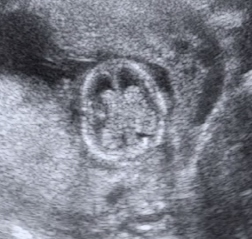

Na megérkeztünk dokitól. Mondanom sem kell hogy nagyon rendi volt. Férjem is bent volt velünk végig. Az UH-t egy nagy plazma TV-re "vetítette" ki így nagyon jól láttunk mindent.

Újra azt mondja a doki h a mérete alapján több 13 hétnél a babó...

Érdekes... Én nem bánom mondjuk ha előbb jön picit!!! :lol:

Kaptunk egy szép színes képet és a videófelvételt az UH-ról.

A doki azt mondja nem nyilatkozik de nagyon dudorodik vmi a lába között... :lol:

Szóval Mumi lehet h két tökös Bercink lesz!!!

A képeket a videóból vágtam ki...

Kép Kép

itt látszik a kuki

Az agya tisztára olyan mint egy dió!!! :lol:

Itt a kezecskéjét és az öklét látni...

A végén pedig a hátát mutatta nekünk, mintha azt mondaná: Na ennyi elég volt mára, szeretnék pihenni!